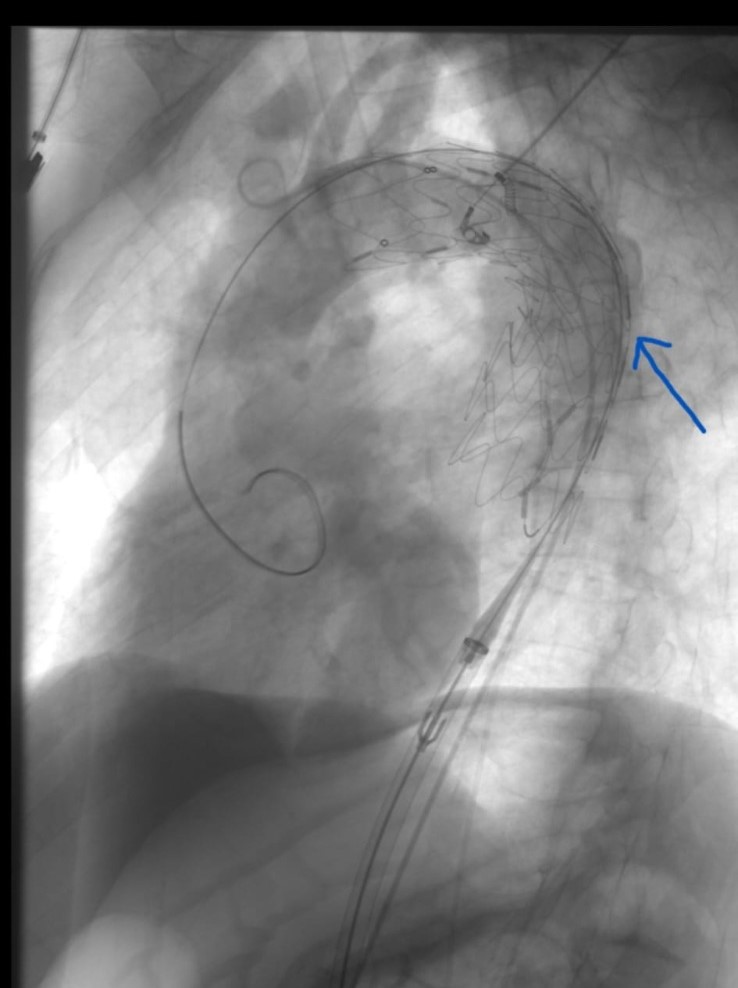

Cerrahi ile teknolojinin birlikte kullanıldığı ve Türkiye’de az sayıda merkezde yapılabilen özellikli ve nitelikli ameliyatlar artık Karaman Eğitim ve Araştırma Hastanesinde de gerçekleştiriliyor. İlimizde göğüs ve karın bölgesinde Aort denilen en büyük atardamarın balonlaşması nedeniyle hastaneye yatırılan 65 yaşındaki A.B.Ç isimli bir hastaya eşzamanlı olarak hem göğüs hem de karın bölgesindeki balona açık cerrahi uygulamadan kapalı olarak başarılı şekilde müdahale edildi. Konuyla ilgili olarak Kalp Damar Cerrahisi uzmanlarından Op. Dr. Sencer KILIÇ ve Dr. Öğr. Üyesi Osman Yaşar Işıklı yapmış oldukları açıklamalarda şu ifadeler yer verdiler:“Aort denilen vücudumuzun en büyük atar damarın karın bölgesindeki balonlaşması genellikle herhangi bir yakınmaya neden olmadan sessizce genişler ve patlamaya yol açar. Bu durumdan muzdarip hastanın %80 i kaybedilir. Ameliyata ulaşmış hastalarında riski yüksektir. Kanamaya yol açmış tüm hastaların en çok %10 ile 20 si taburcu olmaktadır. Risk altındaki kişilerin anevrizma olup olmadığı önceden saptanabilirse cerrahi ya da endovasküler (TEVAR /EVAR) girişim ile yaşam tehlikesi ortadan kalkar. Sigara ve genetik faktörler balonlaşmada rol oynar.65 yaş ve üzeri grupta her 65 erkekten birinde bu hastalık görülür. Erkeklerde bayanlardan 5 kat daha sık görülmektedir. Ülkemizde her yıl 3500 ile 4000 arası kişide tehlikeli balonlaşma olduğu tahmin edilmektedir. 65 yaş ve üzeri erkekler kalp ve damar cerrahisi uzmanına başvurması gerekir. Sigara içiliyorsa veya ömür boyunca 5 paketten fazla içildi ise ailede bu hastalığa sahip olanlar varsa risk daha yüksektir. Basit görüntüleme yöntemleri ile ana damarlarda balonlaşma olup olmadığı saptanabilir. Her balonlaşma girişim gerektirmeyebilir. Damar çapına göre takip edilebilir veya girişim yapılabilir. Çok geniş balonlar açık ya da kapalı yöntemlerle tedavi edilebilir. Hangi yöntemin seçileceğine; kişinin yaşına önemli sağlık sorunların olup olmamasına balonlaşma yerine göre karar verilir.5 yıl önce Türk Kalp ve Damar Cerrahisi Derneği “İçimizdeki Balon” başlıklı halkı bilinçlendirme kampanyası başlatmıştı Karaman’da da son 5 yıldır bu tür balonlaşmalara başarılı şekilde hem açık hem kapalı müdahale edilmektedir. En son 1 hafta önce hem karnında hem de göğsünde tehlikeli balonlaşma görülen A.B.Ç isimli, 65 yaşındaki hastamıza eş zamanlı hem göğüs hem de karın bölgesindeki balona açık cerrahi uygulamadan kapalı olarak başarılı şekilde müdahale edildi. Bu gün ise hastanın taburcu edilmesi planlanmaktadır. Ülkemizde sayılı kliniklerde Kalp Damar Cerrahisi, Girişimsel Radyoloji ve kimi zaman Kardiyoloji tarafından bu tür işlemler yapılmaktadır. Anestezi ve Reanimasyon Uzmanlarından Dr. Öğr. Üyesi Tayfun ET, Uzm. Dr. Mehmet Serdar Şencan ve Beyin Cerrahisi uzmanlarından Op. Dr. Gökhan Reşitoğlu’nun desteği ile anjio odasında kısa sürede gerçekleştirilen hem TEVAR hem de EVAR yöntemi ile eş zamanlı uygulanan endovasküler işleminin Kalp Damar Cerrahları tarafından Karaman’da uygulanabiliyor olması hastamız için büyük şanstır. Geç kalmış olsa da yıllardır kullandığı sigarayı bırakmış olan hastamıza uzun ömürler diliyoruz.”Böyle nitelikli ve özellikli ameliyatların Karaman Eğitim ve Araştırma Hastanesinde başarıyla yapıldığını aktaran Karaman Eğitim ve Araştırma Hastanesi Başhekimi Doç. Dr. Halil İbrahim TAŞCI, “ ilimizde bu tür ameliyatın yapılmasının gururunu yaşıyoruz. Hastanemiz bu tür ameliyatları yapma imkânına ve teknik donanıma sahiptir. Bundan sonra da bu tür ameliyatları gerçekleştirmeye devam edeceğiz. Bu ameliyatı gerçekleştiren hekimlerimize ve ekibine çok teşekkür ediyorum." ifadelerini kullandı.